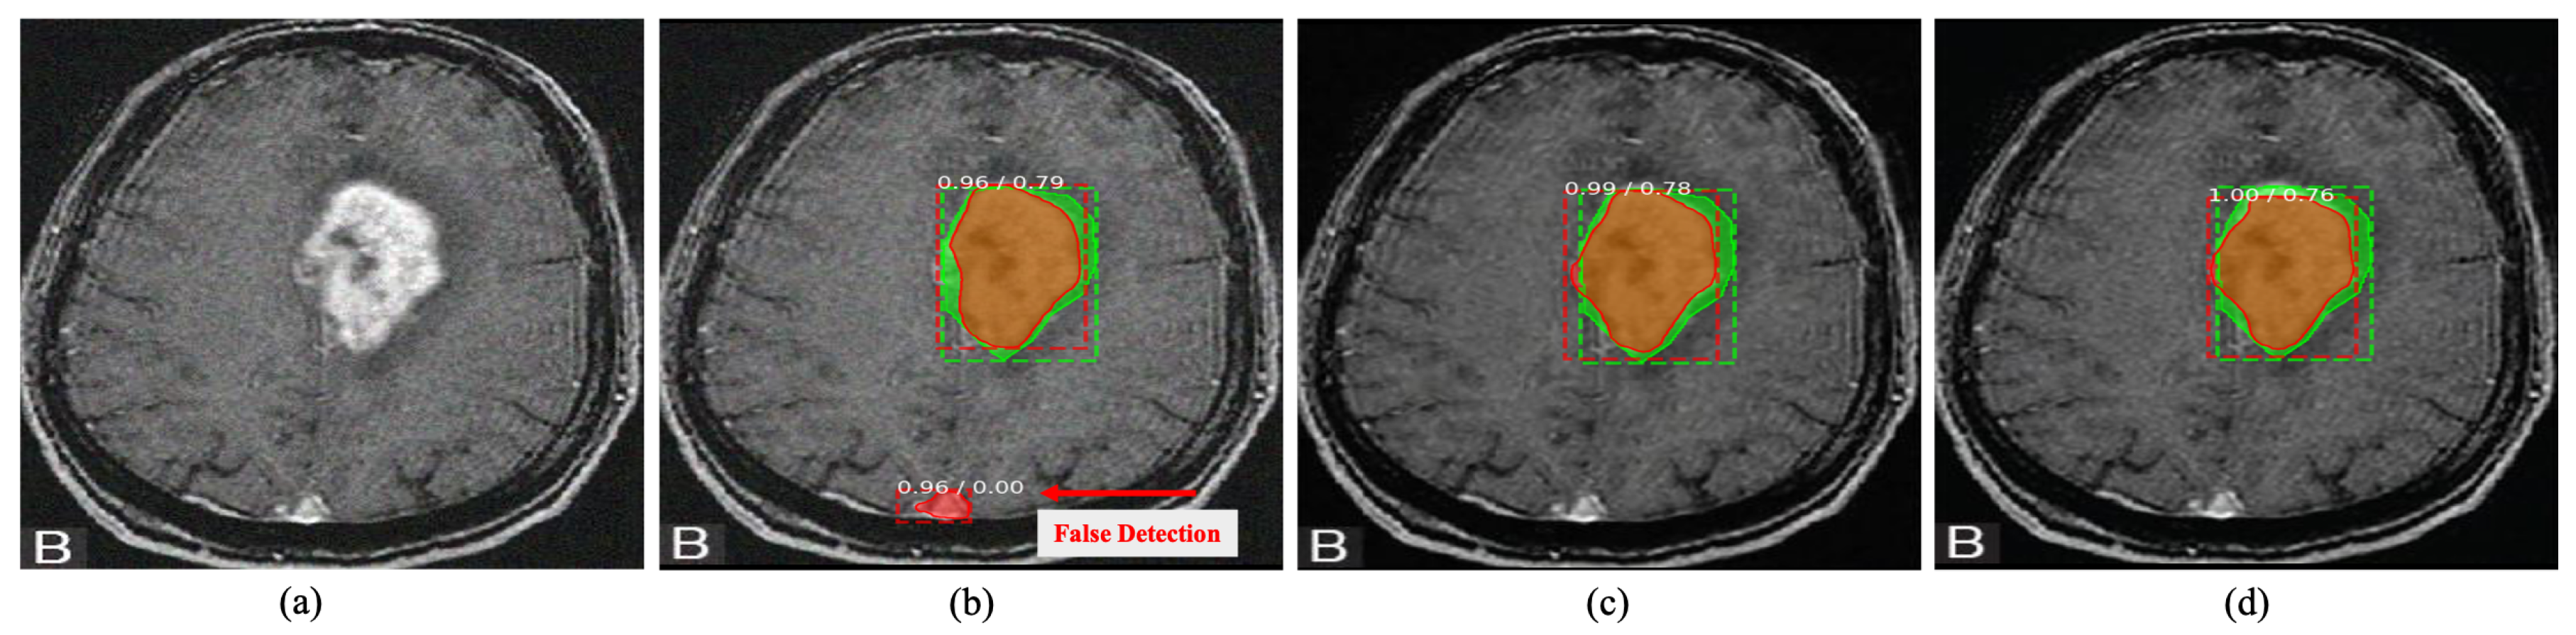

Computer-aided detection has obtained momentum in medical image analysis by observing the oversights of given images [65,66]. However, the presence of sensor noise in a given image can misguide the detection system, as shown in Figure 9. Here, the effect of image noise has studied over tumour detection and localization on brain MRIs using state-of-the-art Mask R-CNN [67]. It can be apparent that even the well-known learning-based method struggle in localizing the abnormalities on a noisy image. Contrarily, the addition of proposed DRAN drastically improve the localization performance of the respective detection method by performing denoising.

Figure 9. Tumour detection on brain MRI image. The green box indicates the ground truth region, while the red box indicates the detected area. The proposed DRAN can improve the localization performance of the detection method to localize the abnormalities by removing the noise present in the target image. (a) Noisy image. (b) Noisy image + Mask R-CNN [67]. (c) Denoised image obtained with DRAN + Mask R-CNN [67]. (d) Reference clean image + Mask R-CNN [67]. Source by: (https://www.kaggle.com/mateuszbuda/lgg-mri-segmentation).